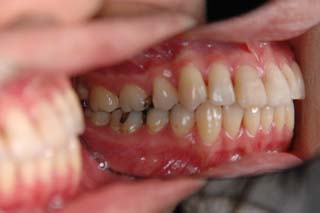

(叢生/正中変位/上右小臼歯抜歯(片顎片側抜歯)/ ハーフリンガル)

骨格的な非対称や治療前に見られた咬耗など、対処が難しい問題もありますが、前歯部被蓋、臼歯関係ともに良好です。今後、保定管理を継続する予定です。